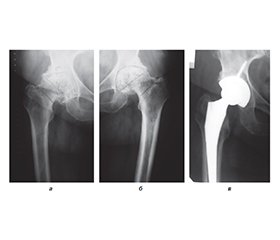

Актуальність. Проблема діагностики та профілактики післяопераційних коагулопатій доволі актуальна у сучасній ортопедії, оскільки в Україні й за кордоном зростає кількість операцій ендопротезування пацієнтам з різною патологією кульшових суглобів. Мета: на основі аналізу факторів ризику розвитку венозних тромбоемболічних ускладнень (ВТЕУ) у хворих із патологією кульшового суглоба до та після операції ендопротезування обґрунтувати комплекс заходів їх профілактики. Матеріали та методи. Пацієнтів, яким проводилось ендопротезування кульшового суглоба, було розділено на групи: І група — низького ступеня ризику віком 20–40 років (n = 13); ІІ група — помірного ступеня ризику віком 41–60 років (n = 45); ІІІ група — високого ступеня ризику віком 61–80 років (n = 42). Для оцінки ступеня ризику тромботичних ускладнень використовували методику, аналогічну шкалі J.F. Caprini. Результати. Аналіз тромботичних ускладнень у досліджуваних групах хворих після операції тотального ендопротезування кульшового суглоба у порівнянні з даними наукової літератури показав, що ускладнення у вигляді тромбоемболії легеневої артерії у наших пацієнтів не спостерігалося, а за даними літератури — від 1,08 до 30 %, тромбози глибоких вен нижніх кінцівок у нашому дослідженні — 4,65 %, а за даними літератури — 10–20 % (зменшення в середньому на 5,35 %). Набряк нижніх кінцівок (хронічна венозна недостатність) у наших пацієнтів — 15,5–20,9 %, за даними літератури — 17–25 % (зменшення в середньому на 3 %). Висновки. Тромбопрофілактика венозних тромбоемболічних ускладнень при операції тотального ендопротезування кульшового суглоба потребує індивідуального підходу до пацієнтів з огляду на фактори ризику як у доопераційному, так і у післяопераційному періодах. Запропонована нами програма профілактики в досліджуваних пацієнтів, якщо порівнювати з даними літератури, дозволила зменшити кількість тромботичних ускладнень: у І групі хворих з низьким ступенем ризику ці ускладнення не відмічалися, у ІІ і ІІІ групах тромбози глибоких вен нижніх кінцівок зменшилися на 5,35 %, набряки нижніх кінцівок — на 3 %, гематоми у ділянці операції — на 1,5 %. Отримані дані свідчать про ефективність і доцільність застосування запропонованого нами комплексу заходів тромбопрофілактики у хворих після ендопротезування кульшового суглоба.

Background. The problem of diagnosis and prevention of postoperative coagulopathies is quite relevant in modern orthopaedics, since an increasing number of patients with various pathologies of the hip joints undergo arthroplasty both in Ukraine and abroad. The purpose: based on the analysis of risk factors for the development of venous thromboembolic complications in patients with hip joint pathology after arthroplasty, to substantiate a set of measures for their prevention. Materials and methods. Patients who underwent hip arthroplasty were divided into the following groups: group I — low risk, 20–40 years old (n = 13); group II — moderate risk, 41–60 years old (n = 45); group III — high risk, 61–80 years old (n = 42). To assess the risk of thrombotic complications, a method similar to the J.A. Caprini score was used. Results. Analysis of thrombotic complications in the studied groups of patients after total hip replacement compared to the data of the scientific literature showed that complications in the form of pulmonary embolism were not observed in our patients. According to the literature, they are found in 1.08–30 % of cases. Deep vein thrombosis of the lower extremities was detected in 4.65 and 10–20 % of patients, respectively (an average decrease of 5.35 %), oedema of the lower extremities (chronic venous insufficiency) — in 15.5–20.9 and 17–25 % of cases (an average decrease of 3 %). Conclusions. Thromboprophylaxis of venous thromboembolic complications during total hip arthroplasty requires an individual approach to patients, taking into account risk factors both in the pre-operative and postoperative periods. The prevention program we proposed in the studied patients, compared to the literature data, allowed us to reduce the number of thrombotic complications: in group I of patients with a low risk, these complications were not observed, in groups II and III, deep vein thrombosis of the lower extremities decreased by 5.35 %, oedema of the lower extremities by 3 %, hematomas in the surgical area by 1.5 %. The data obtained indicate the effectiveness and feasibility of using a set of thromboprophylaxis measures proposed by us in patients after hip arthroplasty.